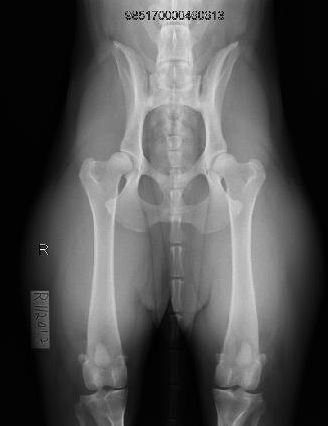

צילומי אגן לוועדת היפ דיספלסיה

בכלבים גזעיים בעלי תעודות יוחסין מבצעים צילומי אגן בהרדמה בדרך כלל מעל גיל שנה. לכל גזע קיים תקנון גידול משלים בו כתוב באיזה גיל ניתן לבצע את הצילום. צילום האגן נשלח לוועדת ההיפ דיספלסיה של ההתאחדות הישראלית לכלבנות המונה שלושה רופאים וטרינרים מומחים ברדיולוגיה.

הכלב מקבל ציון על רמת הפגיעה באגן שלו, הציונים נעים בין A ל E. ציון אגן A לכלב בריא ועל פי חומרת הפגיעה באגן B,C,Dבהתאמה עד לציון E לכלב חולה. בעזרת צילומי האגן נעזרים המגדלים ומבצעים הרבעות מבוקרות על מנת לשפר את הסיכויים לקבל גור בריא שלא יסבול בעתיד מבעיות אגן. צילום האגן נעשה בהרדמה מלאה והוא פעם בחיים ולכן חשוב לבצע את הצילום בצורה הנכונה והמדויקת ביותר.

ד”ר ג’רסי לזר, בשל היותו וטרינר ומגדל של כלבי הקאנה קורסו מבית הגידול Gerassi Corso, פיתח מתקן שעוזר להגיע לשלמות בביצוע הצילום. השלמות במנח הכלב והמהירות בה מגיע ד”ר ג’רסי לזר לצילום המושלם, בעזרת המתקן שלו, למעשה מקצר את משך זמן ההרדמה ובכך בטוח יותר לכלבכם. ד”ר ג’רסי לזר צבר ניסיון רב בתחום צילומי האגן בכלבנות הגזעית ומבצע צילומי אגן לכל גזעי הכלבים משנת 2000. לד”ר ג’רסי לזר רנטגן דיגיטאלי מודרני וחדשני, ובנוסף מעניק יעוץ ועזרה חינם בכל ההליך מול וועדת ההיפ דיספלסיה של ההתאחדות הישראלית לכלבנות.